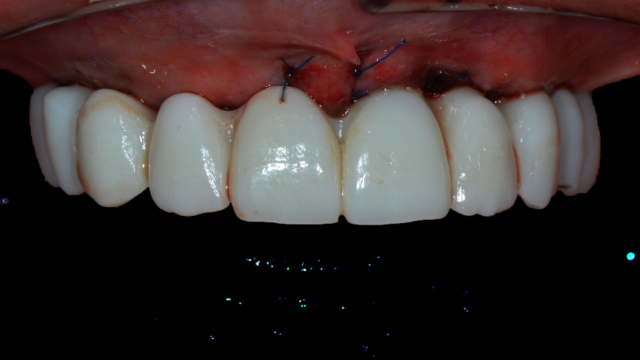

A top set of teeth surgically sewn on to the top of the gums inside a patient's mouth.